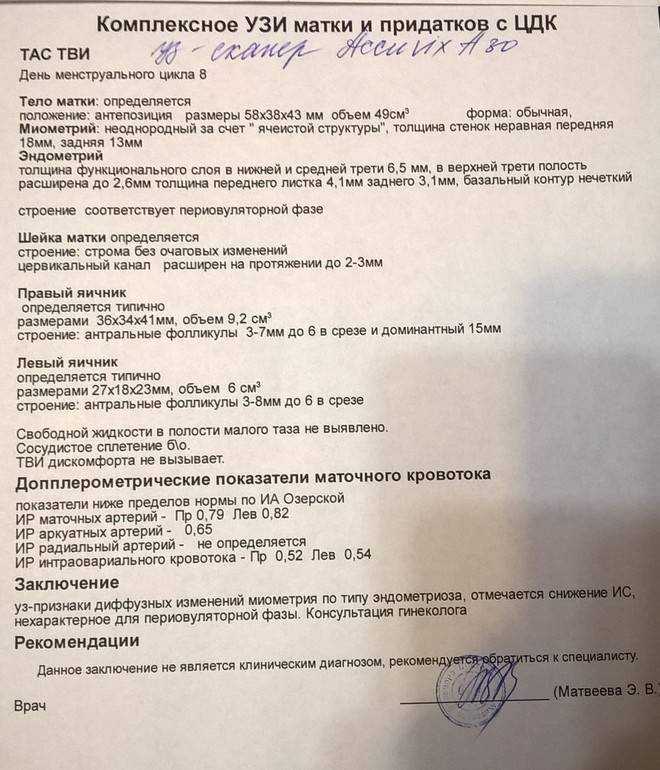

УЗИ малого таза

УЗИ органов малого таза в норме

УЗИ органов малого таза: положения матки

УЗИ ОМТ матка, маточнае трубы, яичники

Почему разные заключения на УЗИ?